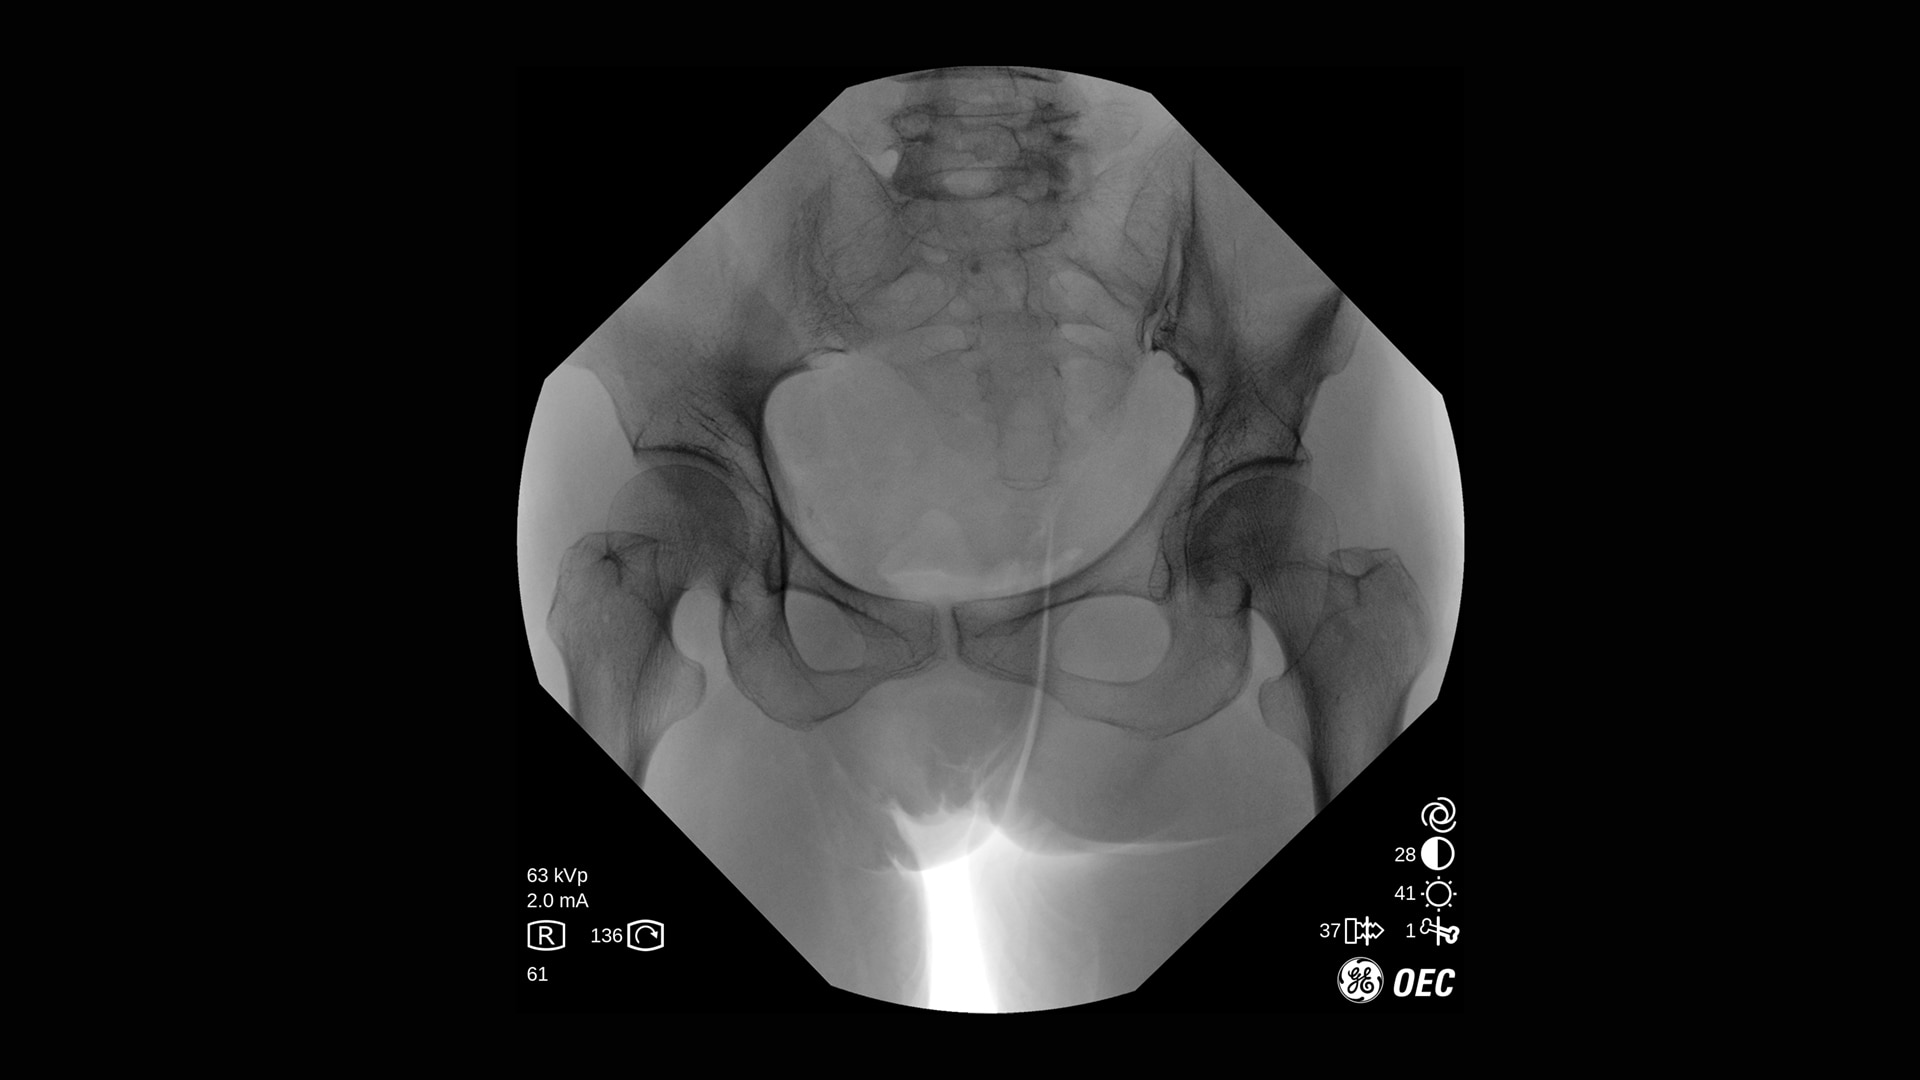

Der OEC One CFD unterstützt ein breites Spektrum klinischer Anwendungen: von endoskopischen Interventionen und Schmerztherapie bis hin zu komplexen Wirbelsäulen- und orthopädischen Verfahren.

Die Bildqualität ist bei verschiedenen Verfahren und Verfahrenseinstellungen essenziell, besonders auf engem Raum. Mit OEC One CFD erleben Sie die Bildqualität, die sie von den OEC mobilen C-Bögen erwarten, sowie die klinische Vielseitigkeit, die bei einem mobilen All-in-One-C-Bogen mit zwei Detektorgrößen benötigt wird.

Der OEC One CFD liefert gestochen scharfe Bilddetails – erfasst mit einem Flat-Panel-Detektor und dargestellt auf einem 27" 4K-UHD-Monitor direkt am OP-Feld.

Optimieren Sie Bildqualität und Dosis mit Live-Zoom, Adaptive Dynamic Range Optimization (ADRO), Bewegungsartefakt-Unterdrückung und weiteren intelligenten Bildverarbeitungsfunktionen.